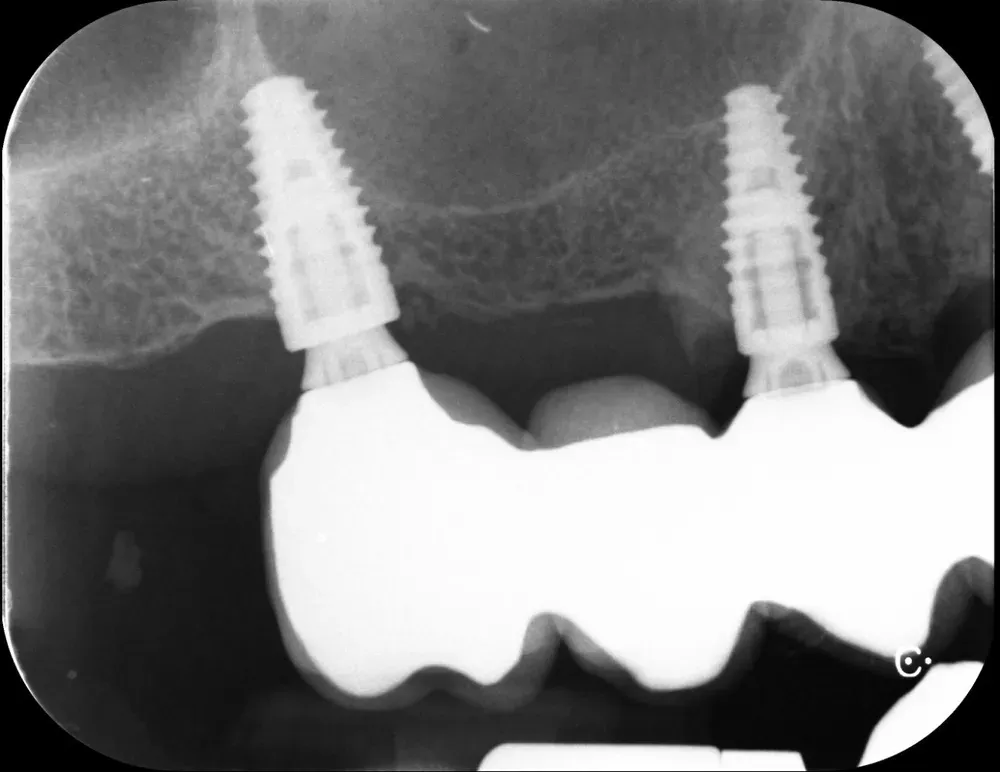

Il controllo a distanza di anni

Al controllo radiografico, sette anni più tardi, gli impianti sono in ottima salute e perfettamente integrati (vedi immagini seguenti).

Francesco viene regolarmente ai controlli, in particolare per le sedute di igiene professionale.